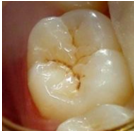

Over the past 20 years, the indication for resin sealant use on occlusal surfaces has changed. Previously, occlusal surfaces were sealed to prevent the development of carious lesions, and were called preventive sealants. In cases where sealants are placed over carious lesions, the term therapeutic sealants is more accurate. Today, sealants are primarily used for therapeutic purposes, aimed at arresting incipient active lesions (6,11,12. For this therapeutic use of sealants, it is essential to assess the extent and activity of the lesion. If the lesion is inactive (photos 1 and 2), treatment is likely unnecessary. However, if the lesion is active, sealant placement can be an excellent option for the patient 12.